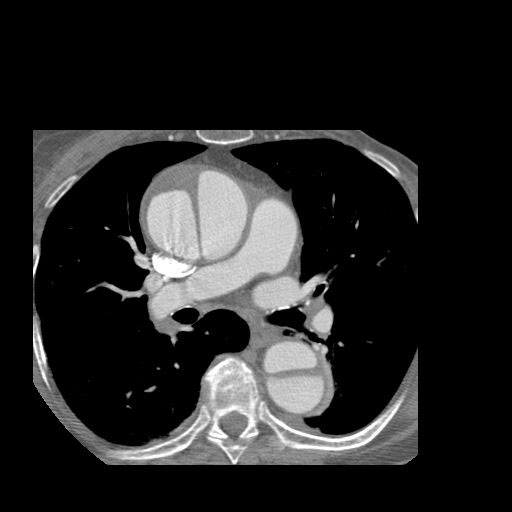

What is going on in this CT?

Ascending and descending aortic dissection